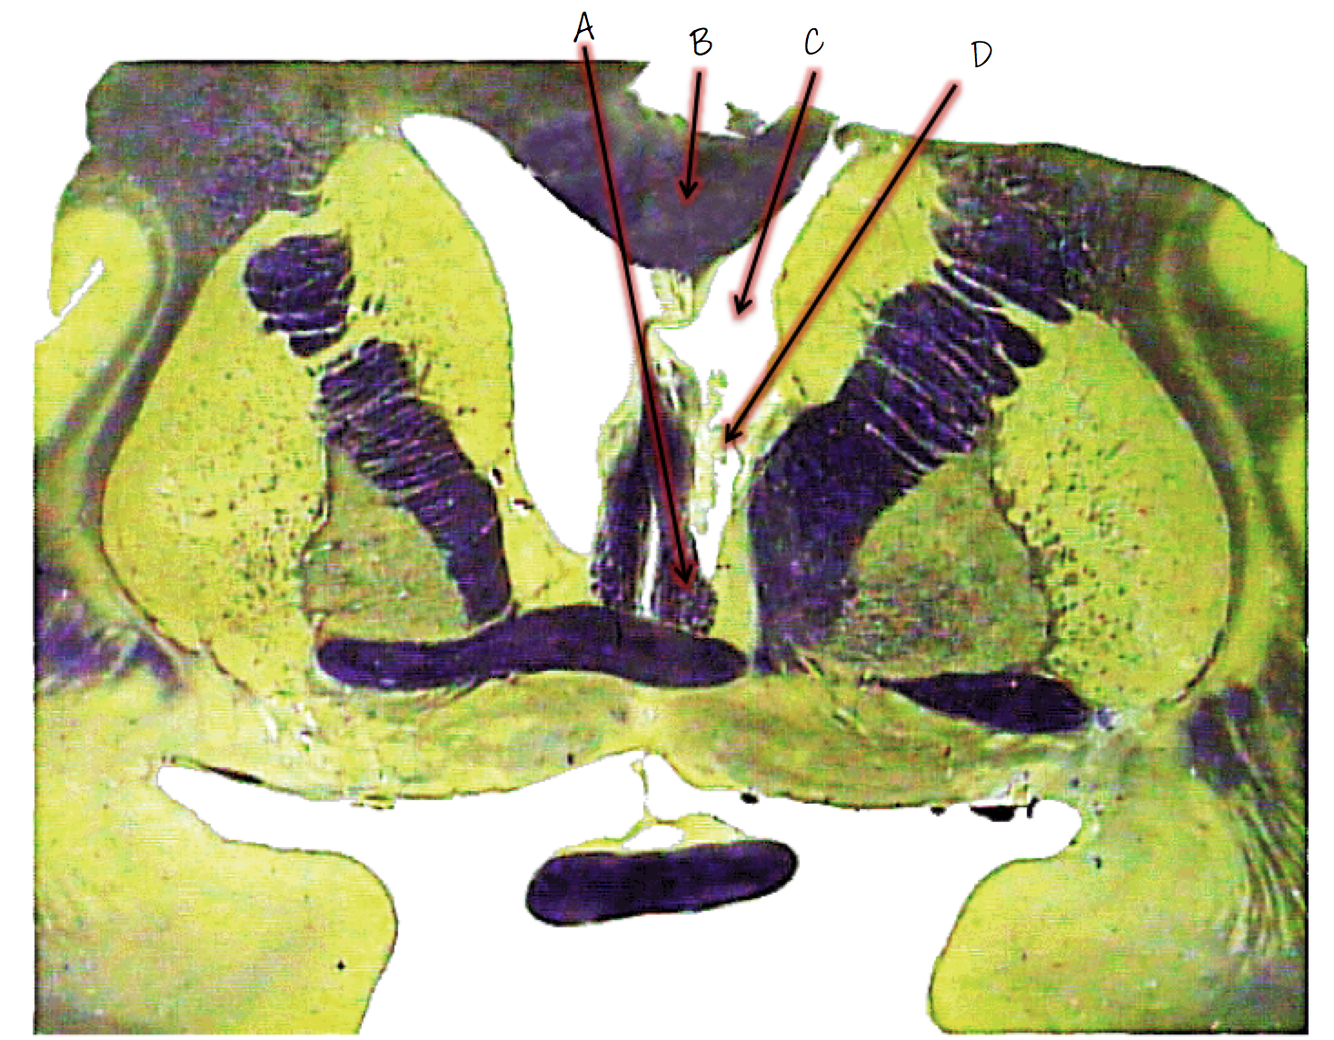

A; fornix

B; corpus callosum

C; lateral ventricle

D; choroid plexus